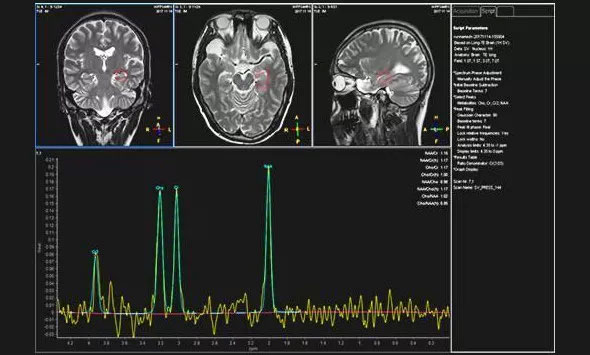

▲患者異常的波譜圖

近日,為求進一步治療,患者就診于上海藍十字腦科醫(yī)院。為完善相關(guān)檢查,醫(yī)院為袁女士進行了頭部MRI增強掃描,檢查結(jié)果與之前的影像檢查一致。為了進一步明確病灶區(qū),醫(yī)院為患者進行24小時腦電監(jiān)測,據(jù)腦電監(jiān)測主任崔麗華介紹,患者為異常視頻腦電圖,左側(cè)額極、左側(cè)顳葉多量尖慢波并發(fā),監(jiān)測期間患者癲癇還發(fā)作了3次。